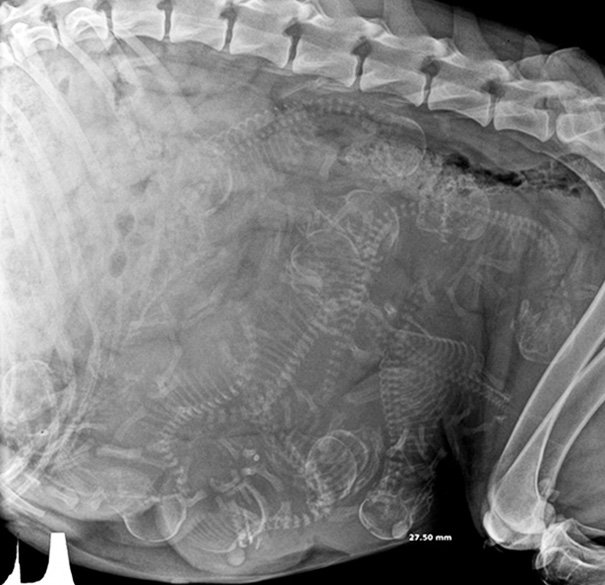

собака